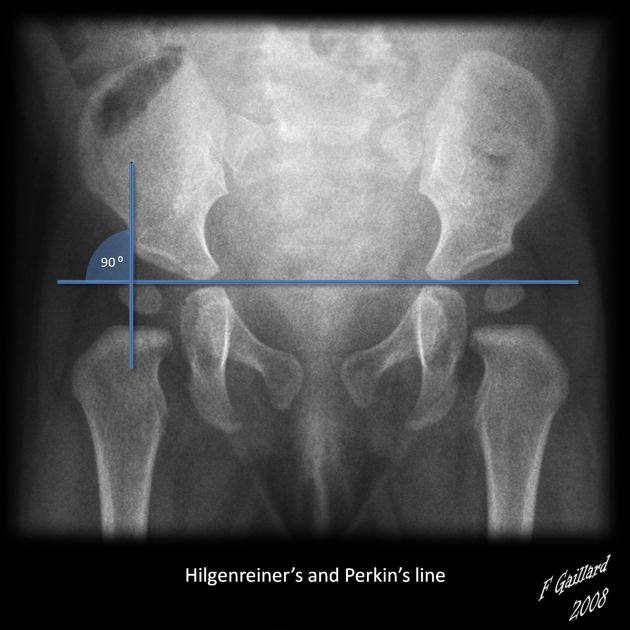

From pediatricimaging.org